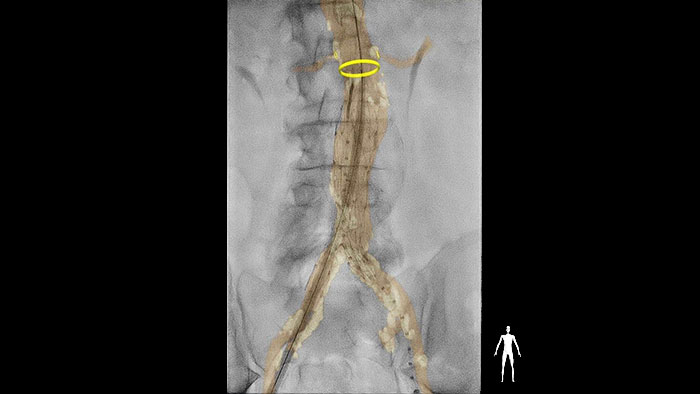

Pour traiter l’épidémie croissante de troubles vasculaires périphériques, nous estimons qu’il faut absolument une certaine uniformisation des stratégies de traitement endovasculaire. Le guidage en temps réel est impératif pendant la procédure pour sélectionner le bon vaisseau, le bon dispositif et la bonne voie d’accès, mais aussi pour positionner précisément les dispositifs afin d’améliorer les résultats cliniques et de développer l’adoption de ces interventions. Dans le cas d’une maladie aortique, l’exposition aux radiations et le produit de contraste sont une préoccupation pour les patients âgés et autrement fragiles. Ces procédures sont longues et souvent imprévisibles. Des procédures plus courtes pourraient réduire l’exposition au produit de contraste et aux radiations.

La suite dédiée au vasculaire a été conçue pour prendre en charge diverses procédures périphériques, aortiques, viscérales, artérielles et veineuses. Qu’il s’agisse de restaurer la perméabilité des vaisseaux, d’implanter un dispositif ou de traiter un anévrisme ou une occlusion, la suite vasculaire permet aux cliniciens de réaliser des procédures rapides, efficaces et simplifiées.